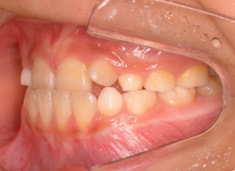

治療前